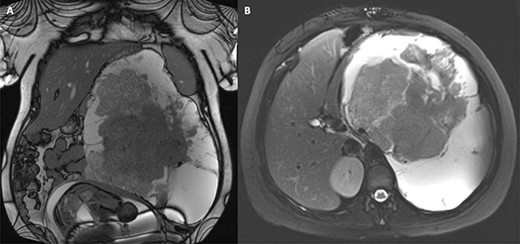

The patient was referred to the regional sarcoma MDT and a further MRI was organised at a 6-week interval to determine the rate of tumour growth. There was minimal interval change in the appearance and size of the tumour, so the consensus opinion at the MDT was to continue surveillance during the pregnancy and delay surgery until the post-partum period. A further two surveillance MRIs were undertaken at 2-month intervals and demonstrated small incremental enlargements (Fig. 1). The plan was to reach 38 weeks of gestation, deliver the baby and excise the tumour a few weeks afterwards, guaranteeing the best chance of survival for both the mother and newborn.

MRI surveillance scan 6 months after diagnosis at 33 weeks of gestation; the tumour and gravid uterus are evident in the coronal view (A), and the tumour occupies the whole left upper quadrant in the axial view (B).